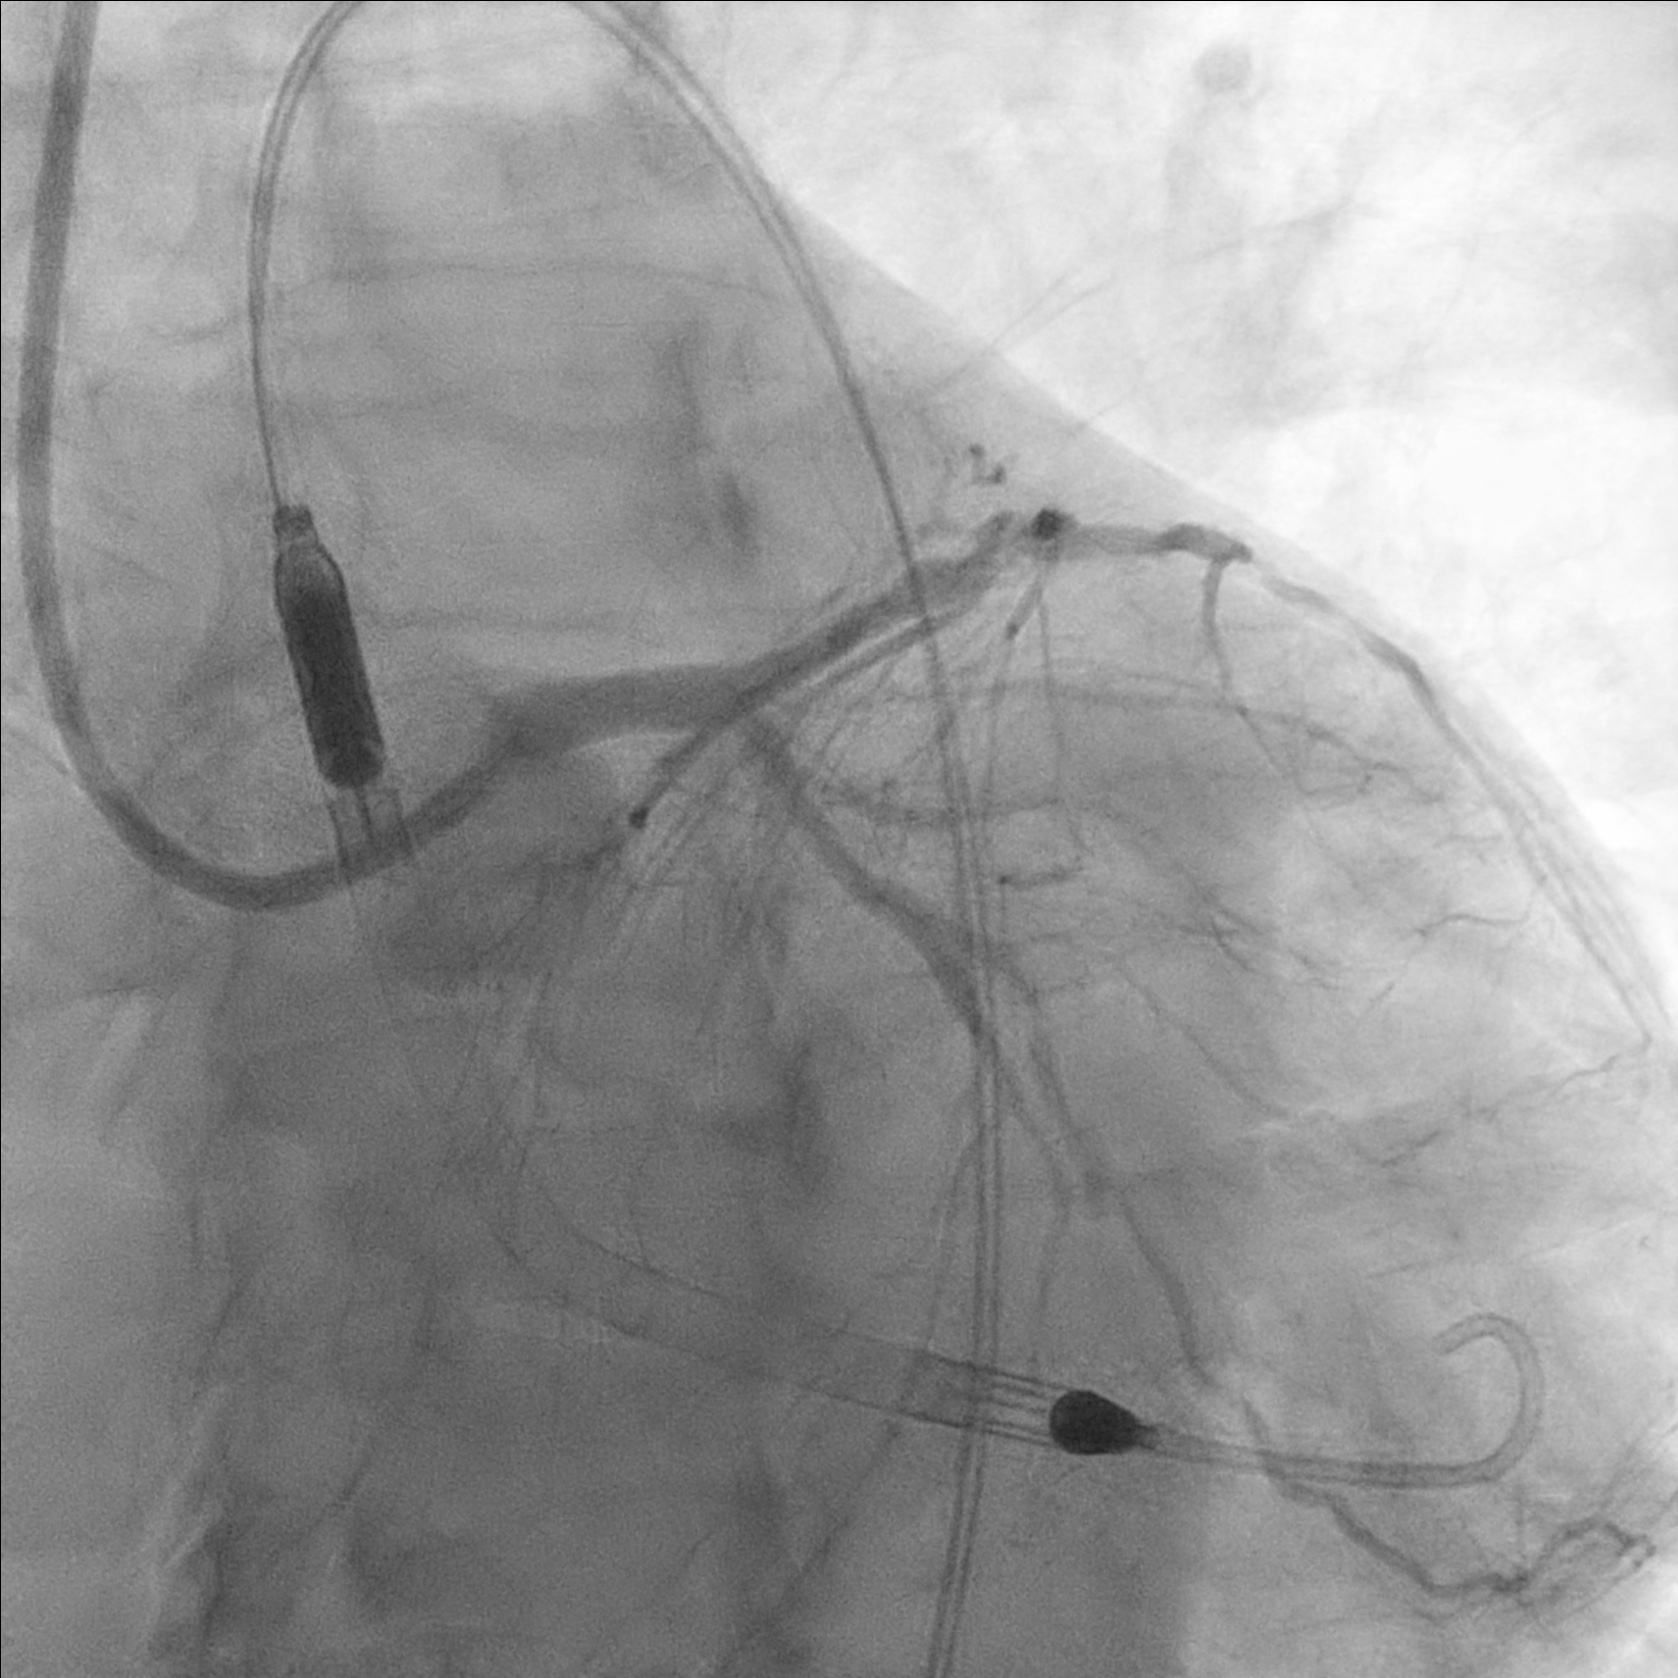

Coronary angiogram showed triple vessel disease and RCA CTO- Left main: normal- LAD: p-mLAD severe disease- LCx: m-dLCx severe disease- RCA: dominant, mRCA total occlusion with retrograde from left system

Impella inserted to left femoral artery due to known right femoral artery stenosis

7-in-6Fr slender sheath inserted to right radial artery. LM engaged with F7 EBU guiding catheter. p-mLAD was predilated with scoring balloon. 2.5/50 DES was deployed to p-mLAD.

7Fr sheath inserted to right femoral artery. RCA engaged with F7 AL1. Attempted wiring with UB3, Fielder XT-A, Gaia Next 2 and Gaia Next 3. Finally successful RCA wiring with Gaia Next 2 by parallel wire technique. Predilation with Scoring balloon. IVUS showed true lumen wiring. A 3.5/50 DES was deployed over m-dRCA, another 4.0/38 DES was deployed over p-mRCA.